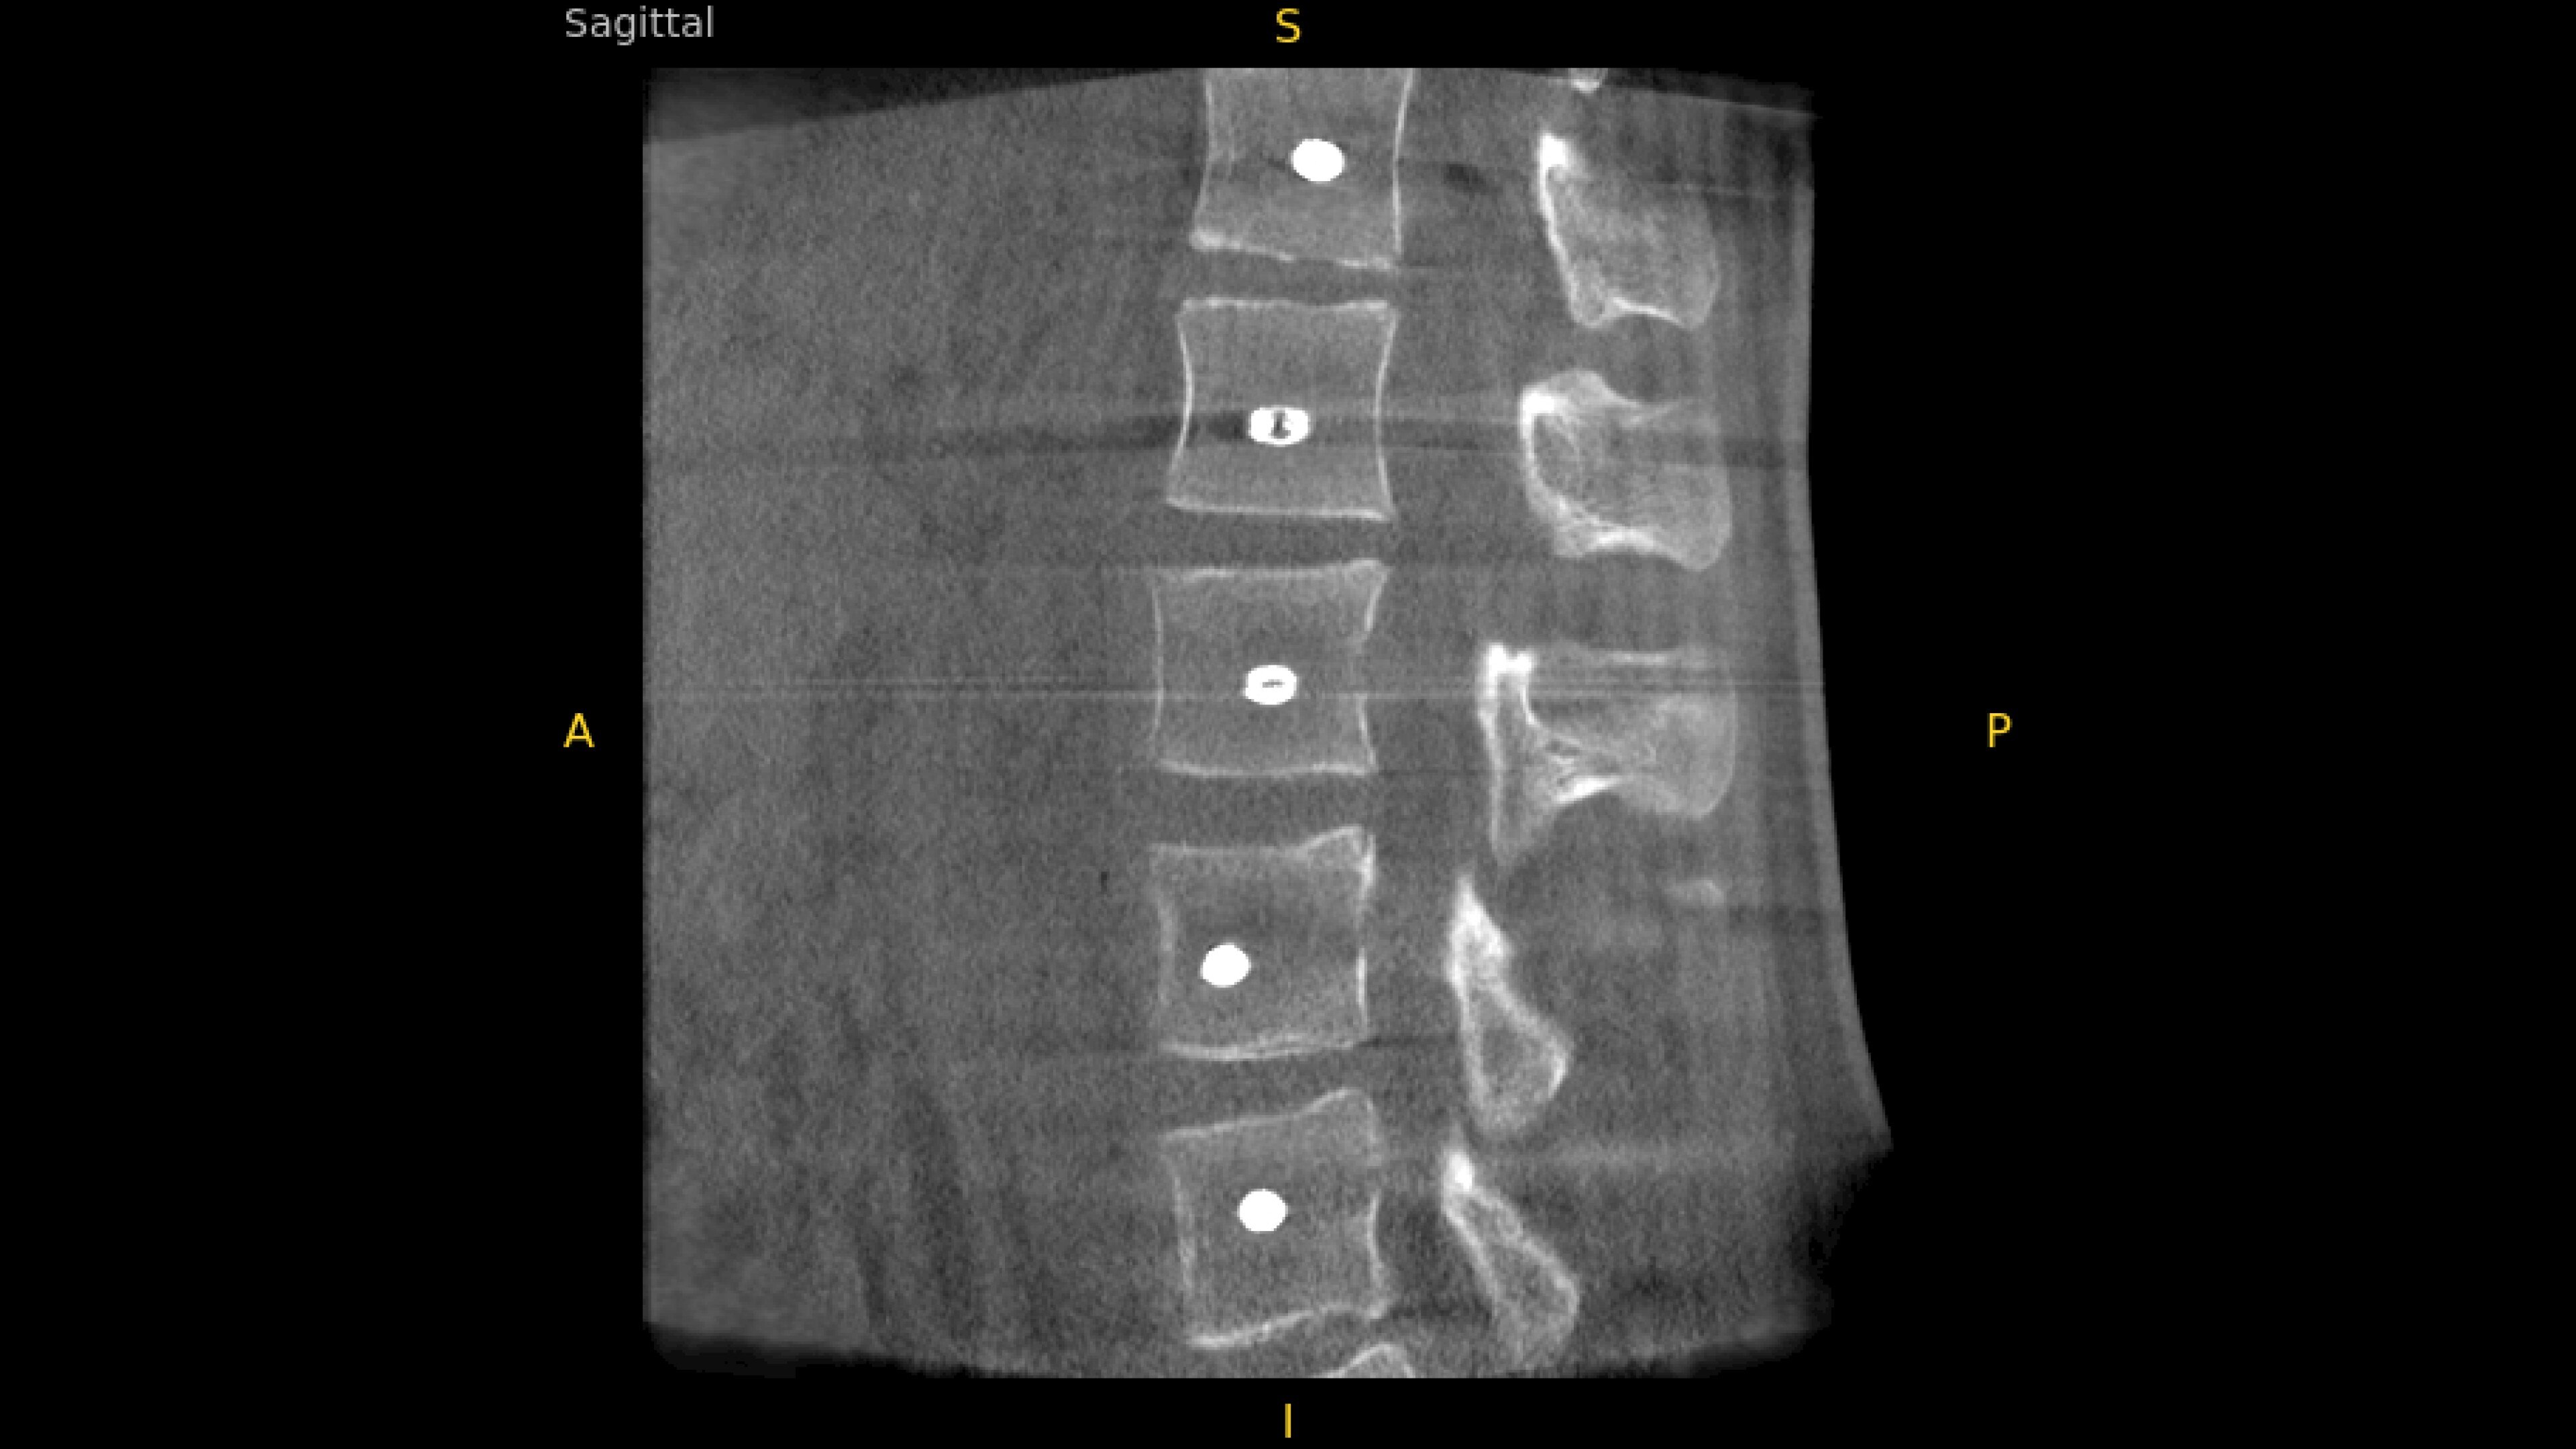

With OEC 3D, comprehensive imaging coverage of 19 cm x 19 cm x 19 cm 3D volumes and exceptional 2D images enables viewing several levels of the spine in the operating room.

The OEC 3D presents five perspectives: Axial, Coronal, Sagittal, MIP, and VR, on a 4K display for clear and detailed review of 3D volumes and 2D images

Review screws with automatic detection and numbering, manually label spine levels, and visualize spinal curvature alignment with Spine Suite, an optional application available with OEC 3D.